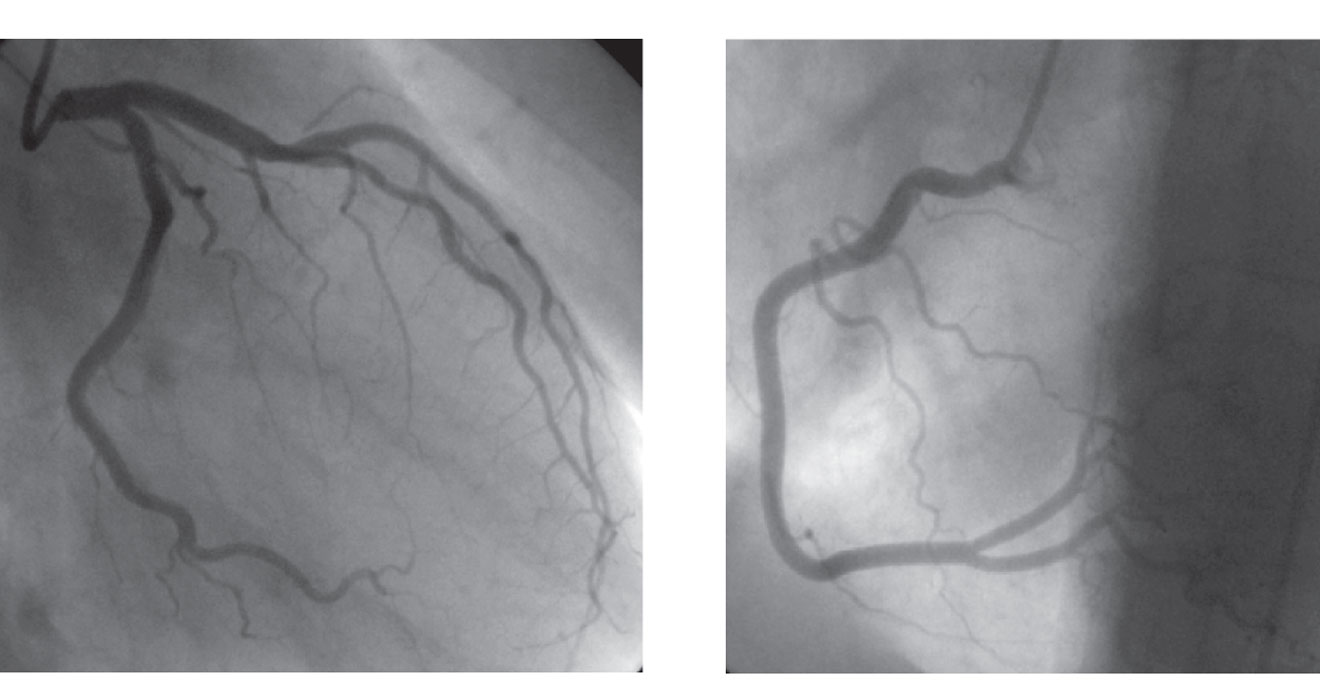

Advanced imaging techniques for accurate heart health assessment.

Specialized procedures to treat challenging coronary artery blockages.